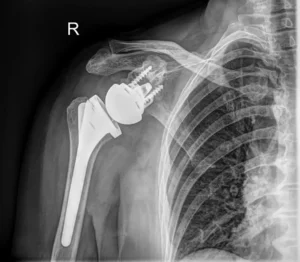

Proteza stawu ramiennego

Rodzaje protez stawu ramiennego

W poprzednim artykule na temat alloplastyki stawu ramiennego poruszyłem kwestię jej popularności w naszym kraju. W poniższym tekście omówię rodzaje protez stawu ramiennego, a także

Alloplastyka stawu barkowego

Alloplastyka stawu ramiennego. Dlaczego jest tak mało popularna w Polsce?

Staw ramienny, choć trzecim pod względem częstości wymiany na protezę zaraz po stawie biodrowym i kolanowym, w Polsce nadal nie cieszy się dużą popularnością. Wiele